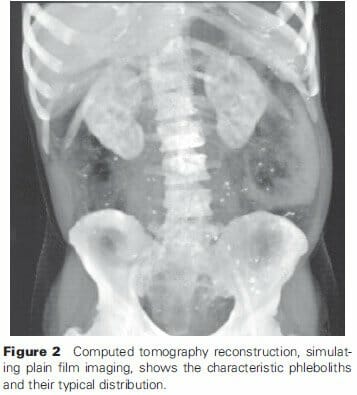

Plain film

As described in the pathophysiology, the sequestration can lead to calcified phleboliths that are evident in 50% of cases31. This largely underestimates the presence of hemangiomas and malformations, due to the calcifications occurring in the colonic wall, and not extending to the soft tissue. The presence of these phleboliths, especially when lateral and outside the pelvic venous plexus are specific signs (Figure 2)33. While rare in the normal population, occurring in less than 5% of individuals under 30, phleboliths appearing in younger patients should raise suspicion to the diagnosis of malformations6,33,44.